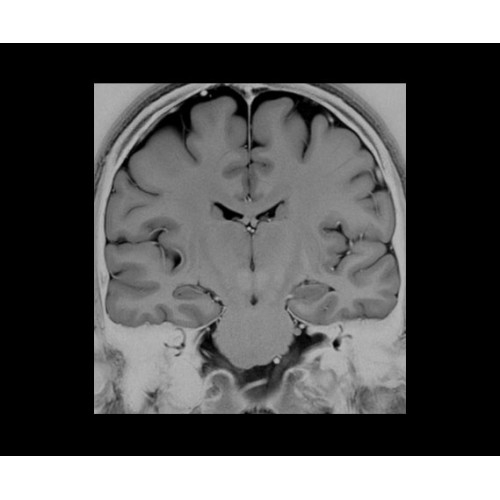

SIGNA PET/MR 3.0T — это гибридная система, в которой совмещаются две принципиально разные технологии — магнитно-резонансную томографию (МРТ) и позитронно-эмиссионную томографию (ПЭТ). Система отличающийся высокой чувствительностью и эффективностью и предназначена для диагностики в области онкологии, неврологии, кардио-васкулярных исследований, исследований воспалительных процессов.

Компания GE Healthcare представляет революционную, полностью интегрированную систему SIGNA PET/MR1, в которой сочетаются времяпролетная технология (TOF) и возможности напряженности магнитного поля 3.0 Тл. Мы поможем вам поднять исследования на более высокий уровень. SIGNA PET/MR позволяет достичь впечатляющей точности и скорости исследований, а благодаря новейшей технологии реконструкции Q.Clear2 качество изображений улучшается в два раза. Кроме того, в систему включен полный набор клинических приложений и гибких катушек для проведения любых видов исследования, открывая для вас возможности визуализации, о которых вы даже не догадывались.

Система SIGNA PET/MR предлагает впечатляющие клинические возможности и открывает доступ к наиболее полным пакетам программных приложений.

Стандартный пакет приложений SIGNA Works позволит вам достичь желаемых результатов в клинической практике благодаря набору высокоэффективных средств визуализации. Программные приложения, входящие в состав данных клинических пакетов, включают широкий спектр контрастов, функции обработки 2D- и 3D-данных, а также возможность коррекции артефактов движения. SIGNA Works предоставляет набор инструментов, необходимых для проведения эффективного клинического исследования.

• Специальный пакет приложений для измерения и сравнения объемных изображений ЦНС с нормами поможет вам в диагностике нейродегенеративных заболеваний, а дополнительные инструменты визуализации — в постановке точного диагноза с помощью бета-амилоидов и радиоизотопных маркеров ФДГ.